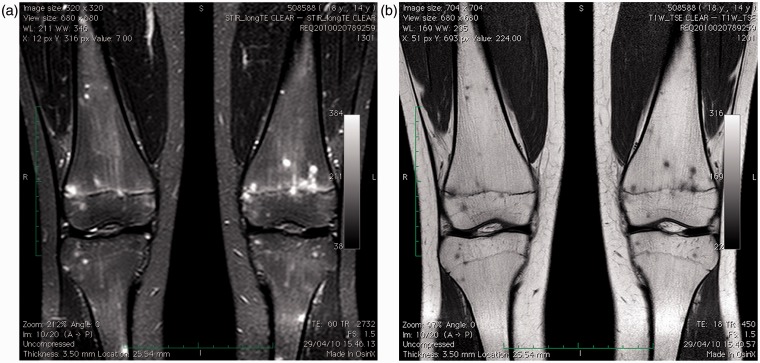

嗜吞噬细胞无原体是一种专性细胞内细菌,是人类粒细胞无原体病(HGA)的病原体,HGA是一种蜱传感染,通常表现为发热、不适、细胞减少、脾肿大和肝炎。在此,我们报告一例14岁的HGA女孩,其全身磁共振成像(MRI)显示了一个不寻常的图像,其特征是小的,广泛的标点毫米结节,t1加权低信号和STIR序列高信号。这一首次报道的发现可能代表了鉴定非典型传染病的另一种工具。

Anaplasma phagocytophilum, an obligate intracellular bacterium, is the causative agent of human granulocytic anaplasmosis (HGA), a tickborne infection usually manifesting as fever, malaise, cytopenia, spleen enlargement, and hepatitis. Herein, we report a case of a 14-year-old girl with HGA whose whole-body magnetic resonance imaging (MRI) disclosed an unusual picture characterized by small, widespread punctuate millimetric nodules, hypointense on T1-weighted and hyperintense on STIR sequences. This firstly reported finding may represent an alternative tool for identifying atypical infectious diseases.